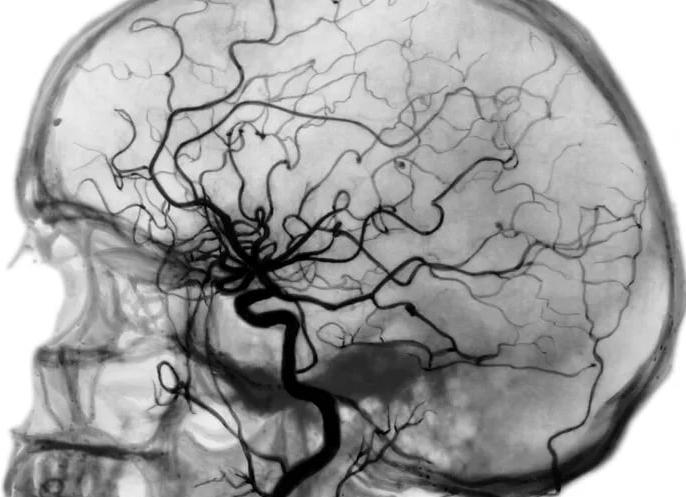

Ангиография сосудов головного мозга применяется для выявления таких патологий, как сужение просвета сосудов, аневризмы, нарушений функционирования почек, сердечных заболеваний, пороков развития внутренних органов, для диагностики новообразований, кист и прочих патологий. Полученный при помощи данного метода снимок дает возможность увидеть сосуды самых разных размеров, во всех органах и системах организма. Часто ангиографию делают перед оперативным вмешательством для точной визуализации опухолей и других патологий, качественной диагностики.

Далее вводят рентгеноконтрастное вещество в кровоток, оно почти непрозрачно для рентгеновских лучей, что формирует четкую картину сосудов головы. Сьемку головы проводят в боковой и передне-задней проекции. Сразу же проявляют снимки и если есть необходимость в дополнительном введении контрастного вещества, повторяют процедуру и делают дополнительные снимки. После того, как контраст пройдет по всем тканям, делают серию снимков, показывающих отток венозной крови. Потом процесс завершают, удаляют катетер или иглу для пункции.

В процессе проведения ангиографии на компьютер выводится несколько рентгенологических снимков (при этом они должны быть сделаны в боковой и переднезадней проекции). В основном, в процессе проведения ангиографии в указанных выше проекциях делают около 5 снимков, если же исследуют кровоток, то количество снимков получается около 20 штук.

Церебральная ангиография сосудов головного мозга – диагностический способ, который дает возможность получить четкие снимки элементов кровеносной системы головного мозга с возможностью создания трехмерного изображения. В силу этой особенности специалисты могут выявить патологические изменения, которые происходят в сосудистой системе органа. Ангиография – это специфический способ, имеющий важное значение для выявления опухолевых болезней мозговых структур.

При осуществлении процедуры в артерию больного вводят рентгенконтрастное вещество, которое позволяет визуализировать сосуды на пленке – именно благодаря этому можно добиться максимальной четкости на изображении.

При изучении изображений, полученных в ходе процедуры, специалист оценивает, в каком состоянии находятся ткани головного мозга, исходя из их формы, плотности, особенностей расположения. Особое внимание уделяется сосудистым сетям.

Ангиография головного мозга демонстрирует конкретные отклонения:

• Измененный диаметр сосуда. Подобное обычно указывает на развитие артериосклероза, сосудистого спазма;

• Ухудшение циркуляции крови, что свидетельствует о внутричерепной гипертонии;

• Расширение сосудистых стенок, которое возникает при аневризме;

Сосудистые сети головного мозга на снимке

• Отклонения в строении сонной артерии. Такой симптом характеризует наличие образований, развивающихся вне мозга;

• Смещение сосудов. На основании данного показателя делают заключение о мозговом отеке, развитии новообразования, нарушении оттока спинномозговой жидкости.

Процедура ангиографии представляет собой введение в кровеносную систему йодсодержащего вещества, что позволяет зафиксировать окрашенные сосуды головного мозга на рентгеновском снимке – ангиограмме.

Интерпретация результатов ангиографии проводится специалистом. По полученной ангиограмме он оценивает структурно-функциональное состояние сосудистого русла. Рентгеновское излучение в зависимости от плотности органических тканей по-разному через них проходит.

Из-за этого на рентгенограммах выглядят:

• кости — белыми;

• ликвор – чёрным;

• мозговое вещество – серым.

Для всех видов сосудов нормальным считается так называемое «ветвление, как на деревьях»: ровные контуры, равномерное сужение просвета. Разнообразные отклонения от этой нормы могут свидетельствовать о различных заболеваниях, которые уже были упомянуты выше. Таким образом, ангиография показывает, какие присутствуют патологии у пациента и как именно их можно излечить.